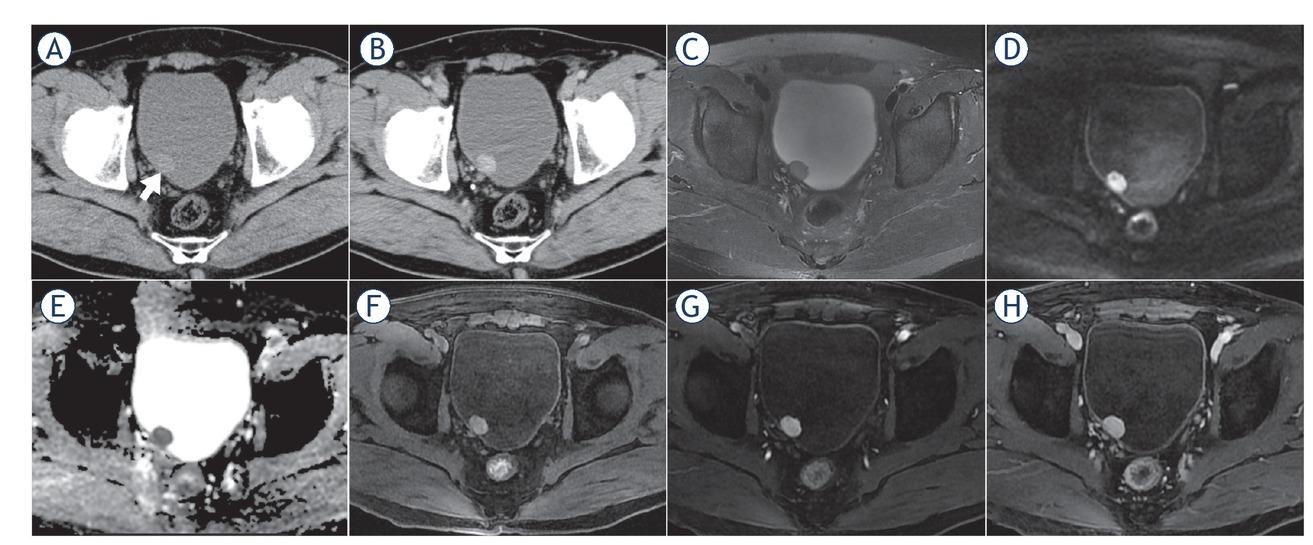

CT and MR image characteristics*

| Computerized tomography (n = 13) | |

|---|---|

| Density | Moderate or slightly lower density |

| Enhancement characteristics | Moderate to marked enhancement |

| Calcification | None |

| Cystic degeneration or necrosis | Rare (n = 2) |

| Haemorrhage | None |

| Magnetic resonance imaging (n = 8) | |

| T2-weighted imaging | Slight hyperintensity |

| Diffusion-weighted imaging | Hyperintensity |

| Apparent diffusion coefficient (ADC) map | Hypointensity (ADC value, 0.883±0.126×10-3 mm2/s)** |

| T1-weighted imaging | Slight hyperintensity |

| Enhancement characteristics | “Fast in and slow out” pattern |